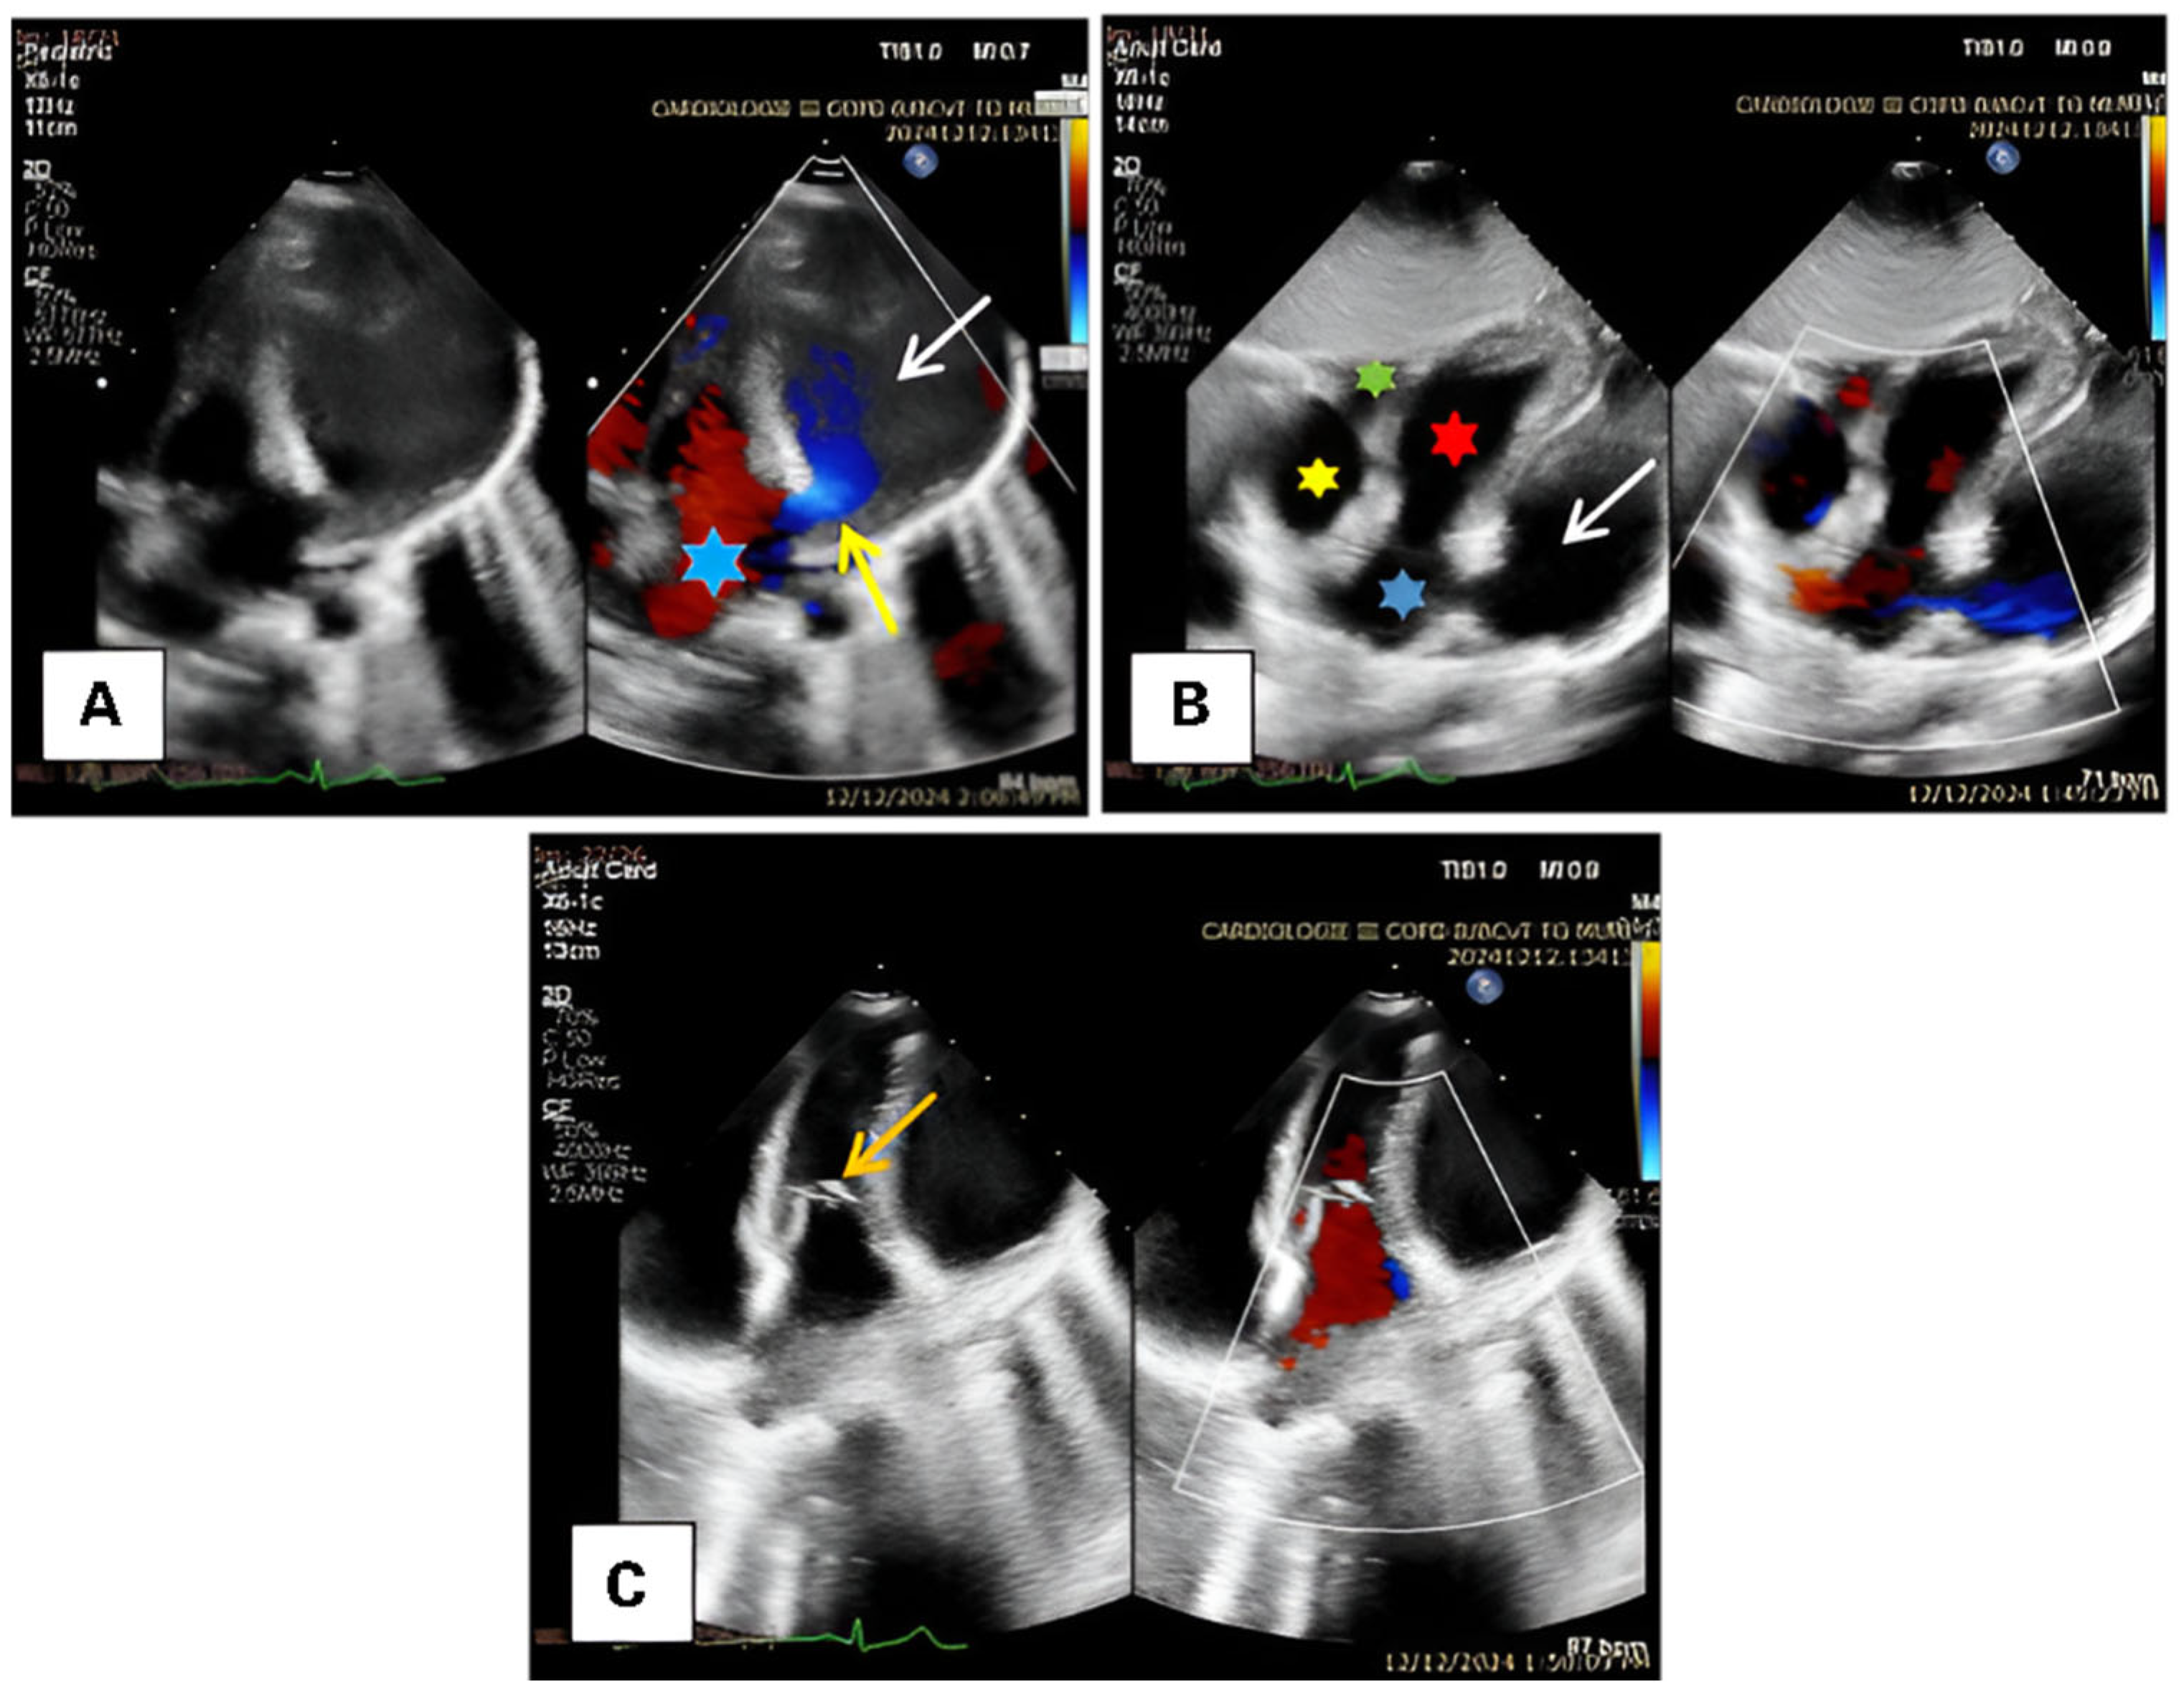

2. Case Presentation